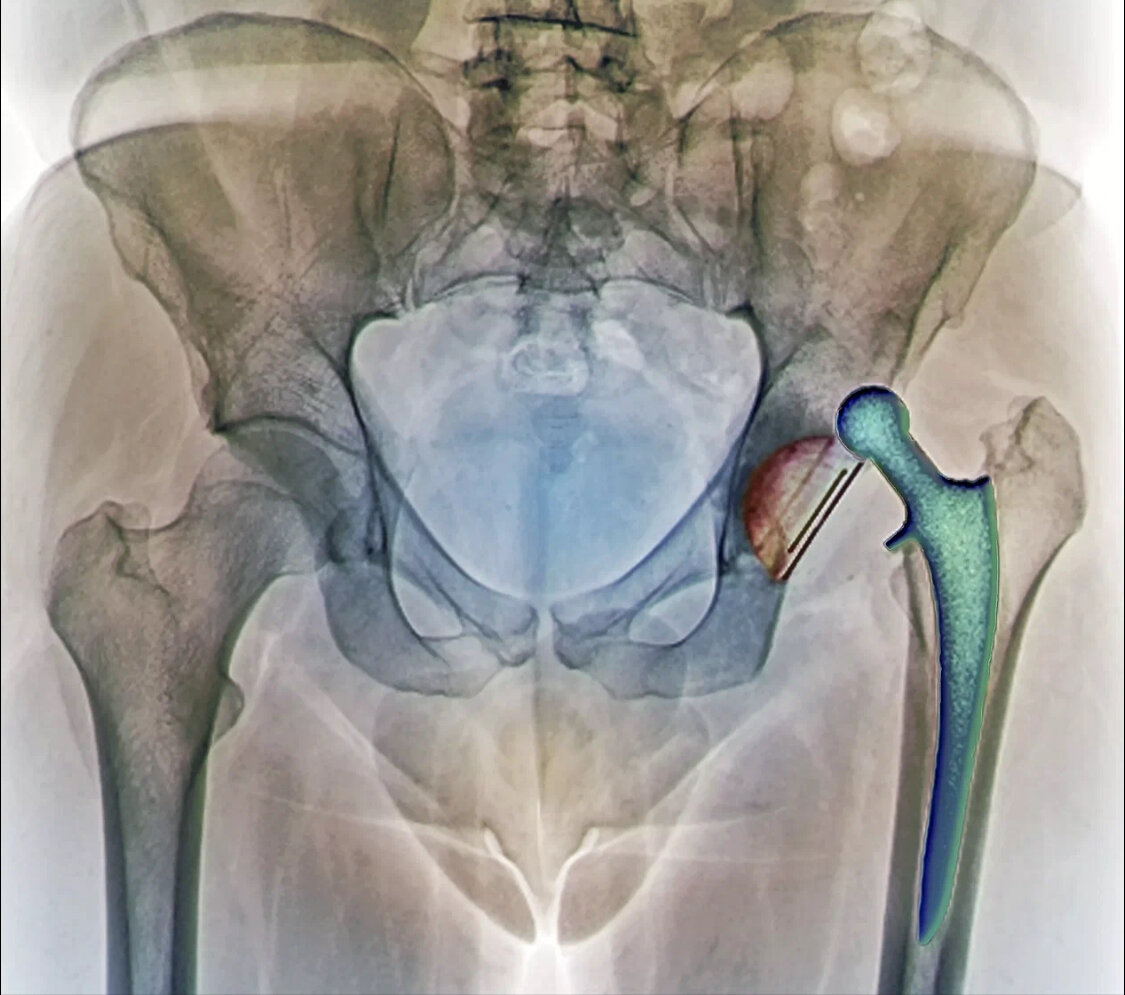

РАЗМЕР ГОЛОВКИ ЭНДОПРОТЕЗА ИМЕЕТ ЗНАЧЕНИЕ

Казалось бы, какая связь? Все, кто интересовался вопросом эндопротезирования тазобедренного сустава, слышали об ограничениях движений после операции. Обычно это следующие пункты, нельзя: В чём здесь проблема? Насколько это верно? Всё довольно просто. Нормальная собственная головка бедренной кости человека довольно большая. Её диаметр обычно от 44 до 54 мм, крайне редко больше или меньше. Такие головки вывихнуть крайне сложно, нужны очень большие усилия и запредельные движения. Когда мы имплантируем искусственный сустав, мы используем искусственные головки меньшего размера - 22, 28, 32, 36, 40 мм. Много лет диаметры 22 и 28 мм были самыми распространенными, затем появилась головка 32 мм, а 22 производить перестали. Сейчас самые ходовые размеры 32 и 36 мм. Были периоды, когда некоторые (крупные!) производители принимались выпускать огромные металлические головки, вплоть до анатомических размеров, но эта тема вновь сошла на нет. Точно так же прекратилось и производство керамических голов

Когда мы имплантируем искусственный сустав, мы используем искусственные головки меньшего размера - 22, 28, 32, 36, 40 мм. Много лет диаметры 22 и 28 мм были самыми распространенными, затем появилась головка 32 мм, а 22 производить перестали. Сейчас самые ходовые размеры 32 и 36 мм.

Итак, сегодня в нашем арсенале головки 28, 32 и 36 миллиметров. Разумеется, они вывихиваются, иное невозможно.

То есть всё, о чем я писал выше, нельзя исключить ни у кого и никогда, но - в некоторых ситуациях вывих бы произошел, если бы стояла головка 28 мм, но стояла 36-я, и вывих не случился. Или 32-я. Миллиметры имеют значение. Пусть разница небольшая, но она есть.